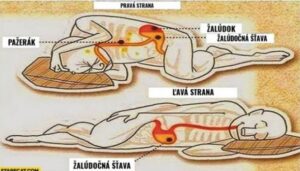

Zánět slepého střeva: 8 příznaků, které byste neměli přehlédnout

Bolest břicha snadno přisoudíme špatnému jídlu nebo nadýmání. Jenže někdy za ní stojí stav, který vyžaduje okamžitou lékařskou pomoc – zánět slepého střeva.